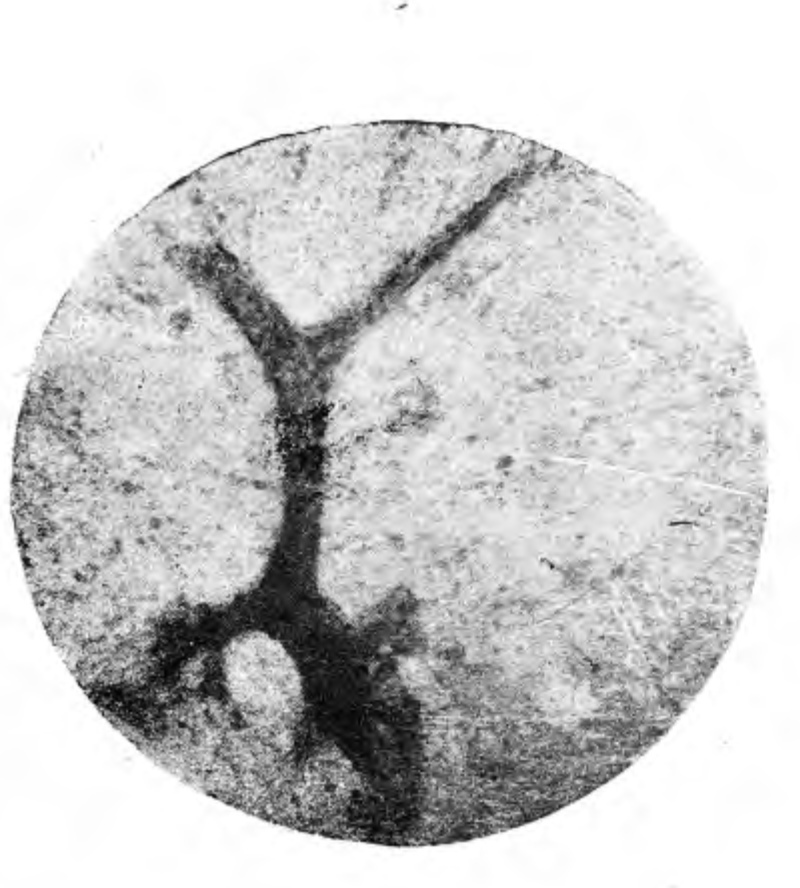

По его указаниям она производится таким образом: из разных отделов- лобных долей мозга вырезаются 1) небольшие кусочки в форме пластинок. При этом они вырезываются так, что захватывается вся толща коры и небольшой, узенький участок белого вещества. Вырезанные кусочки помещают в крепкий раствор сернистого аммония часа на 2—3. Если же мозг очень гнил, то по удалении крышки череда в лобных отделах твердой мозговой оболочки осторожно делаются нужных размеров окна и через них ложечкой (не металлической), так сказать, вычерпываются необходимые количества мозга. В случае нужды, мозговые массы перед сернистым аммонием могут быть уплотнены в алкоголе (но не в формалине), хотя по нашим наблюдениям прибегать к уплотнению можно только в крайности, так как после него уже гораздо труднее получить хорошие, раздавленные препараты, а это, в свою очередь, резко понижает демонстративность микроскопической картины. После обработки аммонием мозг исследуется под микроскопом. Для этого, кусочек при помощи тонкого стеклянного крючка извлекается из аммония, кладется на предметное стекло, покрывается таким же другим и осторожно раздавливается между ними до отказа. На полученных таким образом препаратах уже макроскопически—ясно выступает участок коры, резко отграниченный ют такого же белого вещества. Под микроскопом—надо пользоваться только очень слабыми увеличениями—в корне выступает красивая картина хода сосудов, резко обозначенная черными зернышками сернистого железа (см. микрофотограмму (№1— случ. п.п.). При этом необходимо еще иметь в виду, что кроме этого, специфического для н.п. пигмента в каждом мозгу, особенно в уже загнившем, можно видеть еще отложение другого сорта пигмента, часто также располагающегося по ходу сосудов (или просто диффузно в ткани)—это зернышки и глыбки грязно-желтого или буровато-желтого цвета. Этот пигмент, зависящий просто от гниения, никакого значения не5имеет. Смешение с ним, ввиду сильно отличающего их цвета, на наш взгляд, вряд ли возможно. Чтобы получить хороший, раздавленный препарат, необходимо заранее выбрать пару таких предметных стекол, которые бы хорошо прилегали друг к другу. В противном случае стекла, вследствие своей пружинистости, после раздавливания кусочка, будут отходить одно от другого и этим совершенно портить препарат.

Рис. 1. Сл. paralysis progressiva.